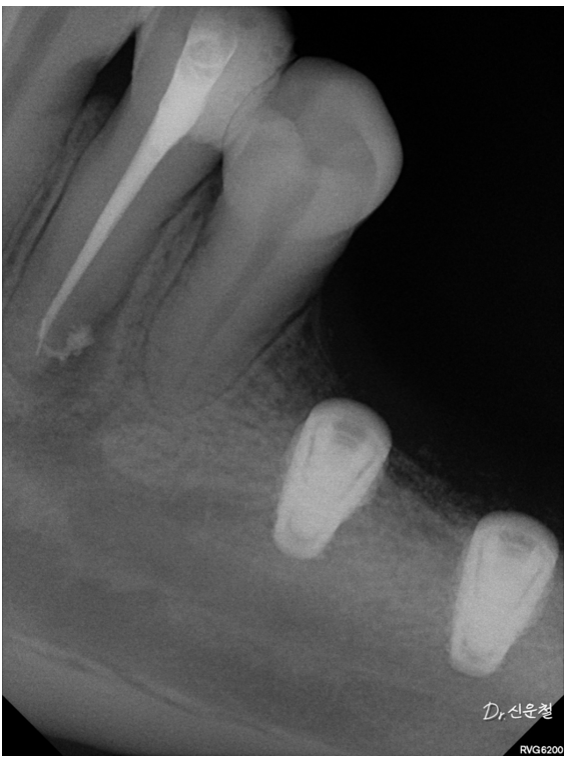

하지만 정밀 검진 결과, 깊게 진행된 사랑니 충치 뿌리만 남은 치아

잇몸뼈가 녹아 흔들리는 어금니 가 확인되었습니다.

통증이 없었던 것뿐,

문제는 이미 상당히 진행된 상태였습니다.

만약 웨딩 촬영 직전 증상이 악화됐다면

발치를 먼저 해야 하는 상황이었을 수 있습니다.